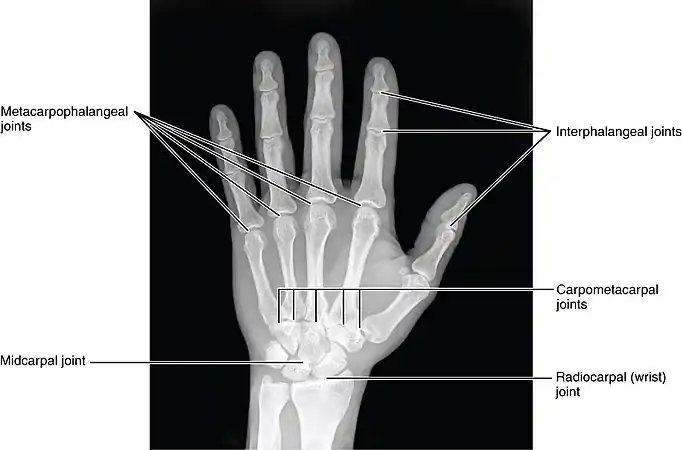

Joints of the hand in an X-ray image